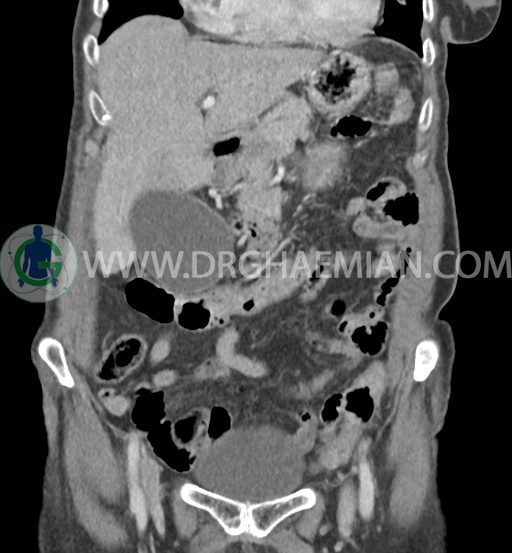

در سی تی اسکن اسپیرال شکم و لگن با و بدون کنتراست خوراکی و وریدی (مولتی دیدکتور 16 با مقاطع ظریف و بازسازی های ساژیتال و کرونال) :

ضایعه ای در معده ، روده باریک و کولون مشهود نیست .

مایع آزاد در حفره شکم و لگن رویت نمی شود. ضایعه ای در مثانه مشهود نیست.

تصویر شبیه به توده به قطر 15mm بین خم کبدی کولون و سگمان 6 کبد و قطب تحتانی کلیه راست و به قطر 8mm در انتریور سکوم مطرح کننده توده های peritoneal

هرنی ونترال در ناحیه اپیگاستر حاوی چربی